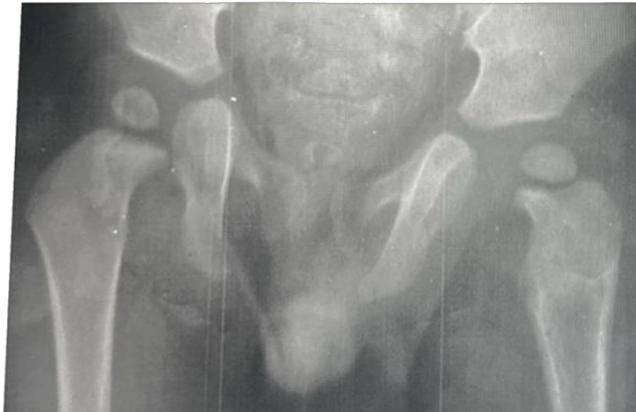

| Neonatal Examination for Developmental Dysplasia of the Hip (DDH) - Ortolani Test / Barlow Test (NOT PART OF OSCE) | Ortolani Test Purpose: Reduces a dislocated hip. Expected finding: Feel a “clunk” (not a “click”). Barlow Test Purpose: Dislocates a reduced hip. Expected finding: Feel a “clunk” (not a “click”). | Ortolani Test technique Purpose: Reduces a dislocated hip - Expected finding: Feel a “clunk” (not a “click”) ![]() Barlow Test technique Purpose: Dislocates a reduced hip - Expected finding: Feel a “clunk” (not a “click”) ![]() Combined Ortolani/Barlow technique ![]() ![]() | |